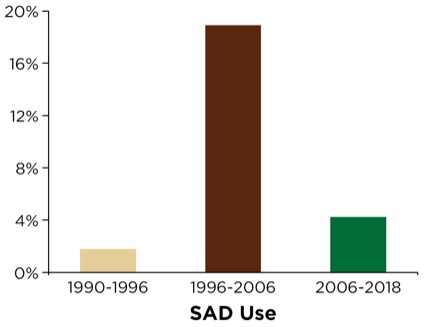

The SAD was used sparsely from 1990 to 1996 (60 deployments in 3,289 cases; 1.8%) due to its relative lack of availability in remote locations outside the OR (Figure 1). The department and institution, commencing with the publication of the American Society of Anesthesiologists’ (ASA’s) difficult airway algorithm, coupled with its comprehensive airway management review and recommendations,2 subsequently organized and distributed difficult airway carts (DACs) within OR and PACU areas as well as strategic and high-traffic NORA locations throughout the institution (e.g., radiology, gastroenterology suite, emergency department, all ICU areas and the cardiac catheterization suites). Additionally, portable/mobile suitcases containing adjunct airway devices and equipment were deployed and carried by the anesthesia stat airway team. The anesthesia stat airway team was primarily responsible for NORA airway management throughout the institution and served as backup and consultants for the emergency department. These suitcases were brought to the patient’s bedside, and contained a variety of primary and secondary SADs as well as other adjuncts, as suggested by the ASA’s recommendations.

SAD use soon expanded substantially; that is, between 1996 and 2006, there were 964 deployments in 5,089 cases (18.9%) following efforts to ensure its ubiquitous availability in NORA settings (Figure 1). Later in 2006, the acquisition and dissemination of video laryngoscopic devices (GlideScope and the portable GlideScope Ranger, Verathon) ushered in the airway team’s transition and rapid embracement of being VL-capable for NORA emergency airway management. Review of the database following VL deployment revealed that SAD utilization underwent a substantial decline; between 2006 and 2018, there were 437 deployments in 10,423 cases (4.2%; Figure 1).

Utilization of the SAD in its role as a rescue ventilation and intubation conduit appears to be undergoing major changes (Table 10). As presented earlier in Figure 1, the use of the SAD peaked following widespread distribution and ready access at the beside for NORA emergency intubations as well as in the OR. In our institution’s “post-ASA guideline ready” period from 1996 to 2006, the SAD was deployed, in some role, in nearly one in six NORA emergency airway interventions. VL was introduced in the mid- to late 2006 and fully deployed to NORA locations in early 2007. There was a precipitous drop in the rescue use of the SAD in 2007, to about 9% following VL deployment. In the following five-year period, its use plateaued in the 4% range.